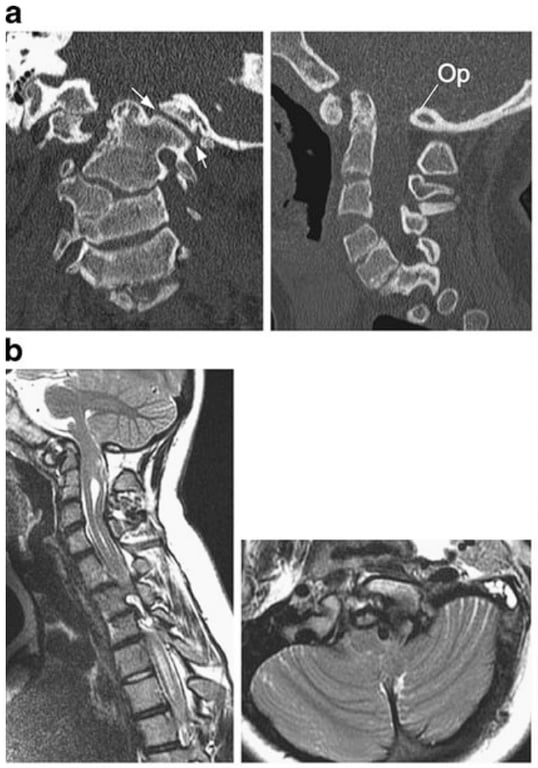

1. CT of CVJ. Left: coronal CT shows severely upslanting and elevated left occipital condyle–C1 joint (arrows). C4 is a hemi-vertebra. Right: sagittal CT shows invagination of the opisthion (Op) (basilar invagination). The posterior arch of C1 is assimilated into the posterior rim of the foramen magnum. Note slightly high-riding odontoid but absence of platybasia, short clivus or retroflexed dens.

1. Sagittal and axial MRI shows compression of the medulla by the invaginating opisthion and syringomyelia